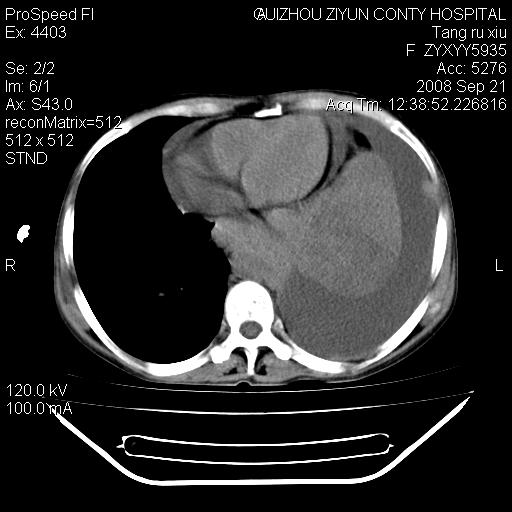

肝脏大小形态尚可,其实质内可见多发大小不等的低密度影,边缘模糊。肝门区结构紊乱,腔静脉腹主动脉旁可见多发软组织密度影,部分融合成团块状,并向下延伸。胰腺及十二指肠结构显示不清。腹腔内脐后肠管走形僵硬,管壁可见增厚。盆腔内可见多个淋巴结影。所扫层面左侧胸腔可见大量弧形水样密度影,其内侧可见被压缩的肺组织影。左侧胸壁可见一小结节样软组织密度影,边缘模糊。心脏纵隔向右侧移位。心脏包膜内可见囊样低密度影,其内侧心房室周围可见一圈气体样密度影。纵隔内大血管旁可见多发软组织团块影,部分融合。

1.腹膜后淋巴瘤侵及肝脏,肺内及纵隔内多发转移。2.左侧大量胸腔积液并压缩性肺不张。3.心包脓肿可能,转移不除外。4.脐后局部肠管管壁增厚,考虑炎症可能,肿瘤不除外。

为什么没有人注意到腹腔脐后的那段肠管呢?那段看着很不好的样子。